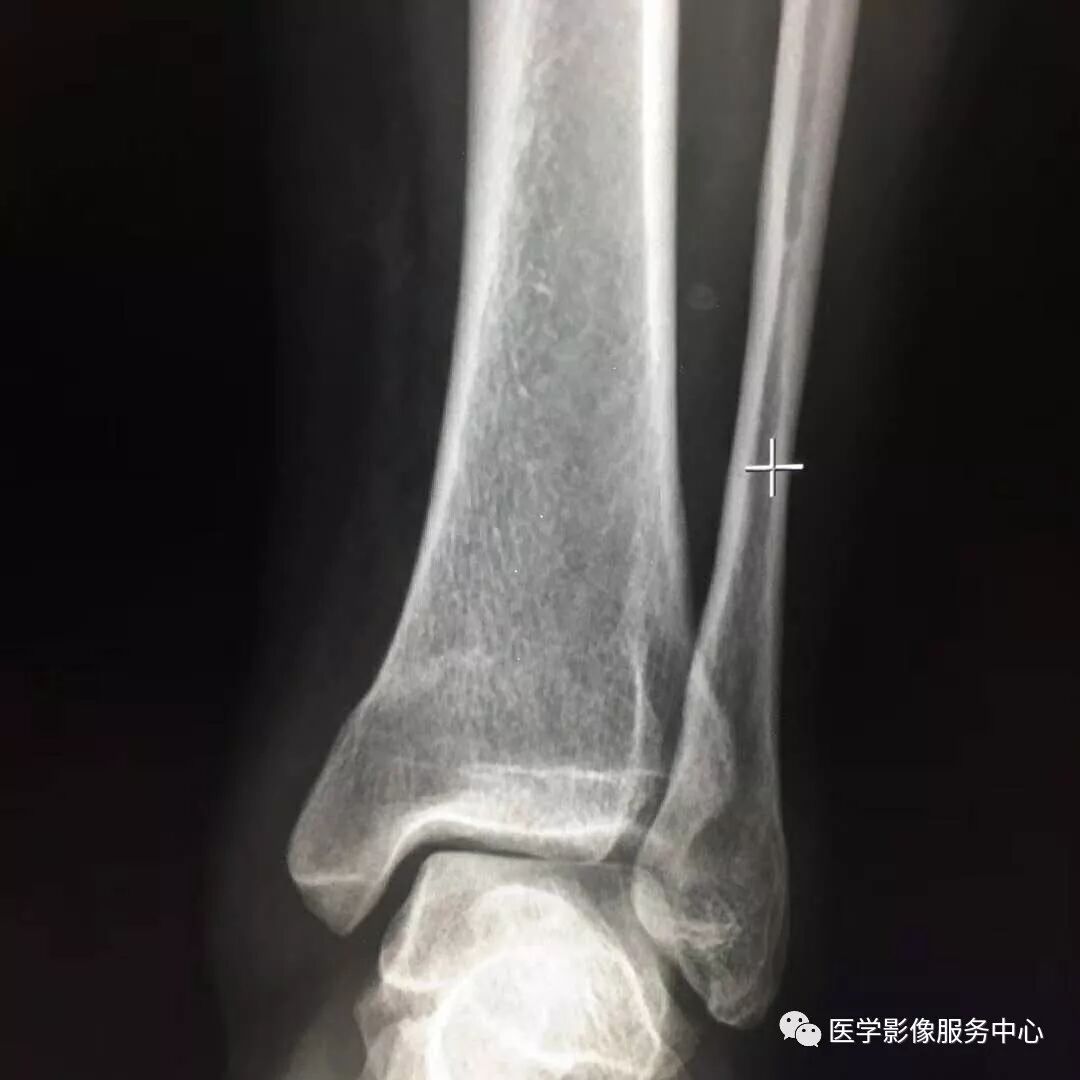

Pilon骨折常常伴随极度粉碎的骨折和严重的软组织损伤,选择合适的手术入路就成了手术的关键。